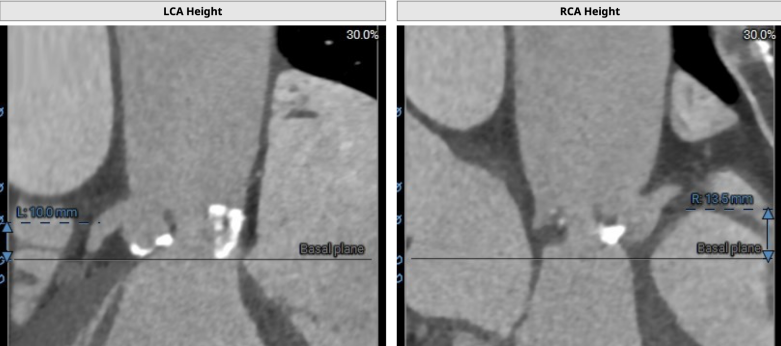

CT分析

主动脉瓣

Type1型二叶瓣,右无融合,瓣环周长折算直径25.4mm,左室流出道周长折算直径29.3mm,瓣环呈开发式结构。

左冠开口高度10.0 mm,瓣叶明显增厚稍长,冠脉阻塞风险高。

手术方案分析:患者为功能型二叶瓣,右无冠窦可见融合,重度钙化1191积分,超声提示主动脉瓣重度狭窄重度返流,左冠高度约10.0mm,左冠瓣叶长,左冠闭塞风险高,术中球囊预扩张行风险评估,根据预扩情况判断是否需要左冠保护。患者双侧髂动脉-股动脉走形稍迂曲,管腔未见明显狭窄,推荐右侧股动脉做为主入路。此外,因患者术前存在严重心衰症状,血压低,LVEF值仅31%,需大剂量血管活性药物维持,TAVR术中循环崩溃风险高,遂决定在体外循环辅助并行循环下操作,使用Venus-Plus二代可回收输送系统,以增强手术安全性。

CT分析

主动脉瓣

Type1型二叶瓣,左右融合,瓣环周长折算直径24.2mm,左室流出道周长折算直径26.2mm。

左冠开口高度9.7 mm,瓣叶上缘达冠脉开口,冠脉阻塞风险高。

手术方案分析:患者为TYPE 1型二叶瓣,左右融合,左冠高度约9.7mm,右冠高度约15.4mm,左冠瓣叶超过冠脉开口上缘,初判左冠闭塞风险较高,拟术中球囊预扩张行风险评估,根据预扩情况判断是否需要左冠保护。术前CT提示主动脉弓呈锐角并钙化,植入器过弓风险高,综合决定首选启明Venus瓣膜L26,22mm球囊预扩,使用有良好过弓性能的启明Venus-A pro三代输送系统,可回收的同时改善过弓难度以及同轴性。患者循环不稳,进行左侧腹股沟区切开,游离股动静脉缝好荷包备用,随时根据需要进行体外循环保护,保障病人安全。